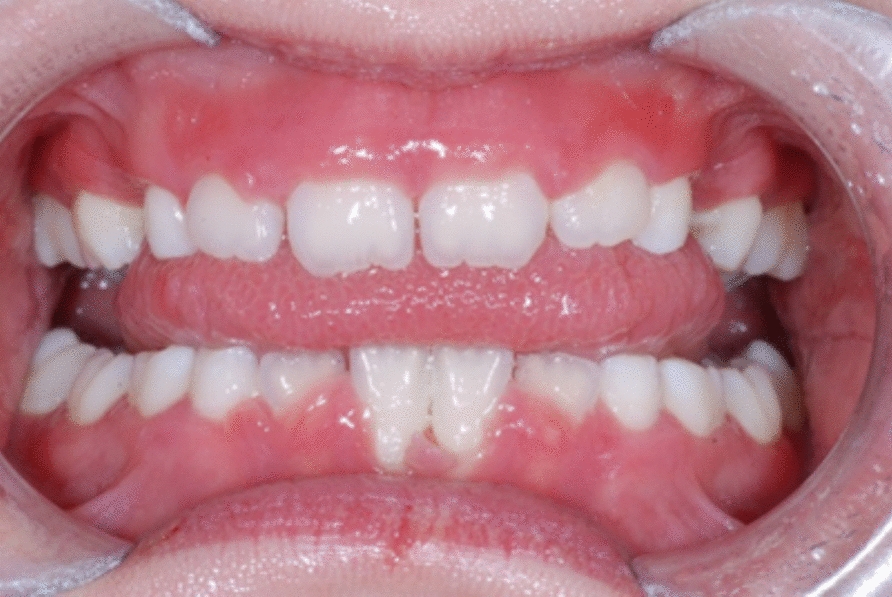

Case presentation: A 6-year-old girl of Swedish descent was referred for evaluation owing to bleeding gums and oral discomfort. Clinical examination revealed dry, cracked lips, inflamed oral mucosa and gingiva, carious primary teeth, and multiple missing permanent teeth. Treatment was performed under general anesthesia, and the patient was placed on a bi-monthly follow-up schedule. After 2 years, her oral health had significantly improved.